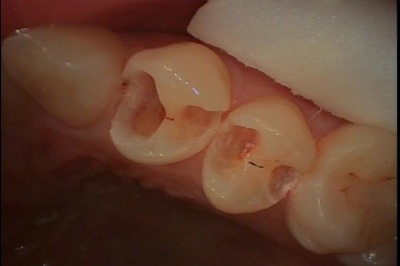

深い虫歯に対し神経を保護し、CR(コンポジットレジン)で修復した例(保険診療)

今回は深い虫歯に対し、神経の保護を行った後、

CR(コンポジットレジン:光で硬化する樹脂製の歯科材料)で修復した例をご覧下さい。

患者さんは都筑区にお住まいの20代の女性の方でした。虫歯の治療を希望されて当院に来院されました。

口腔内所見としては左上第一小臼歯・第二小臼歯が治療途中の状態になっています。

患者さんにお話を伺うといつからこの状態か覚えていないとの事でした。

現在の状態は仮埋めのセメントが充填されている状態だと思われます。

仮埋め状態で長期間放置してしまうと、仮に充填してあるセメントの下が虫歯になってしまいます。

麻酔下でセメントを除去すると下はやはり虫歯になっており、

虫歯を除去するとかなり大きく歯質を失ってしまっています。

- 口腔内所見

- カリエス除去時

かなり大きく、神経に近いところまで歯質を失ってしまっているので、神経を保護する目的で薬剤

(HYc:HYcについてはこちらhttps://www.mitsuishika.com/case/post-58/:)の塗布を行いその後CRを充填し、歯冠修復を行いました。